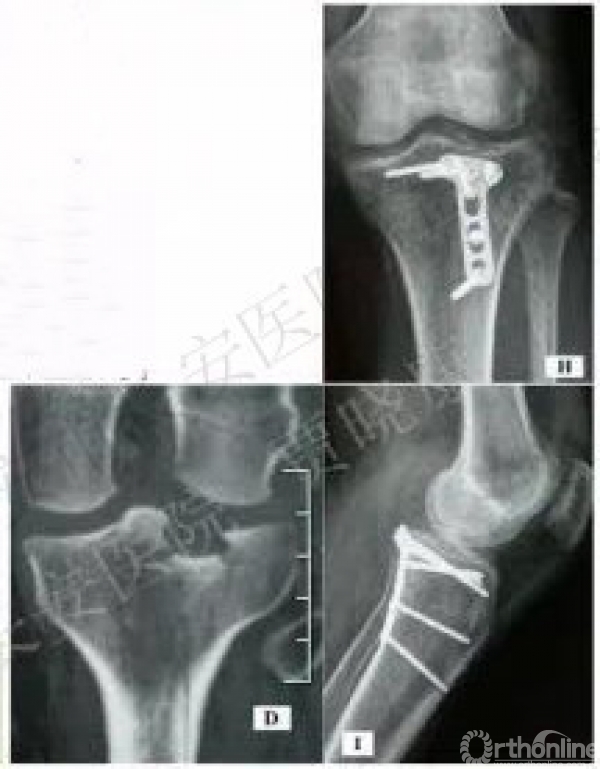

6. 后内L形入路

2010年罗从风

该方法:显露后柱。

适用于:41B2.3x或w、41B3.2x或w、41B1.2可:41B2.1x或u

原文:后外侧入路支撑钢板固定治疗11例胫骨平台后侧劈裂骨折患者。结论:后外侧入路支撑钢板固定是治疗胫骨平台后侧劈裂骨折的一种有效方法,但要熟悉腘窝区解剖结构,正确掌握手术适应证。

7. 改良的后L形入路

2008年王秋根

适用于41B2.1x或u,41B3.1x或u。

原文:改良后外侧入路有助于扩大此类骨折的最佳手术选择,直视下将后外侧剪切骨折的修复固定。